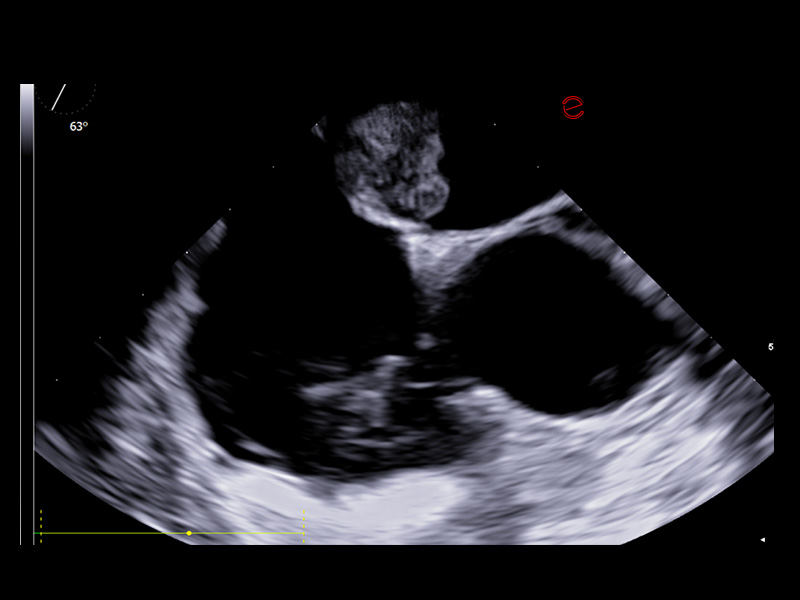

High-performance transesophageal echocardiography probe quality

Esaote’s TEE probe is designed to ensure exceptional image quality and diagnostic versatility, offering detailed visualization of posterior cardiac structures when transthoracic access is limited. It enables precise assessment of the left atrium, appendage, cardiac valves, and thoracic aorta, providing vital information in complex scenarios, such as endocarditis, suspected thrombus, or intraoperative monitoring. Its ergonomic design ensures patient comfort and optimal control during probe manipulation, and its seamless integration with Esaote systems supports real-time guidance for structural interventions and critical diagnostics.